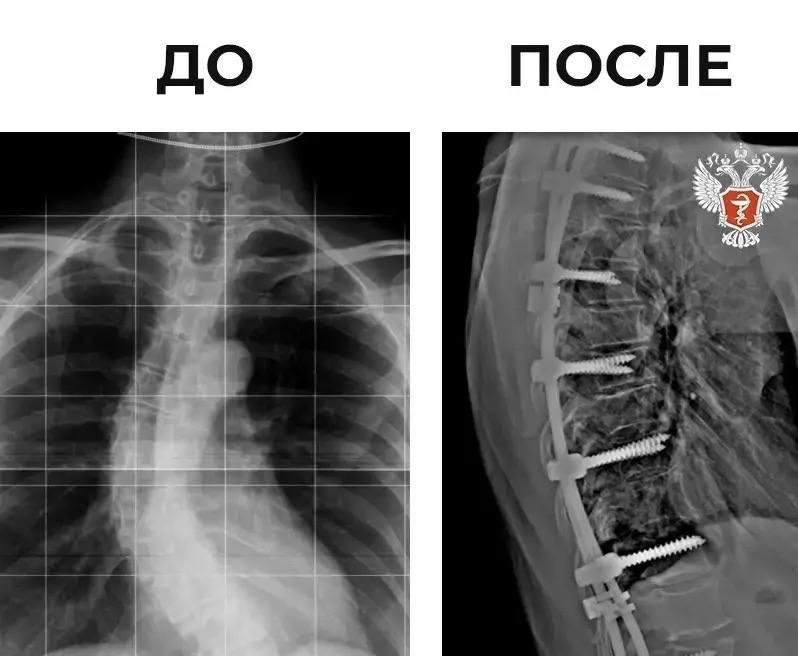

🩺 Нейрохирурги Ярославской области исправили пациентке тяжелый вид сколиоза

57-летняя женщина поступила в Клиническую больницу скорой медицинской помощи им. Н.В. Соловьева с S-образной деформацией позвоночника и постоянными болями в спине.

⚡️ В ходе вмешательства пациентке установили 18-винтовую металлоконструкцию для коррекции и фиксации позвоночника в правильном положении.

Операция длилась три часа и прошла успешно.